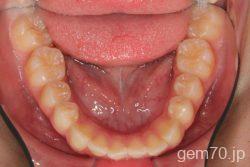

症状:開咬装置:セラミックブラケット | 抜歯世代:10代 | 高校生

主訴)前歯がかみ合わない

診断)開咬

年齢)18歳

使用装置)マルチブラケット装置

治療方法)抜歯 4|4/4|4

治療期間) 2年4ヵ月 通院回数 27回